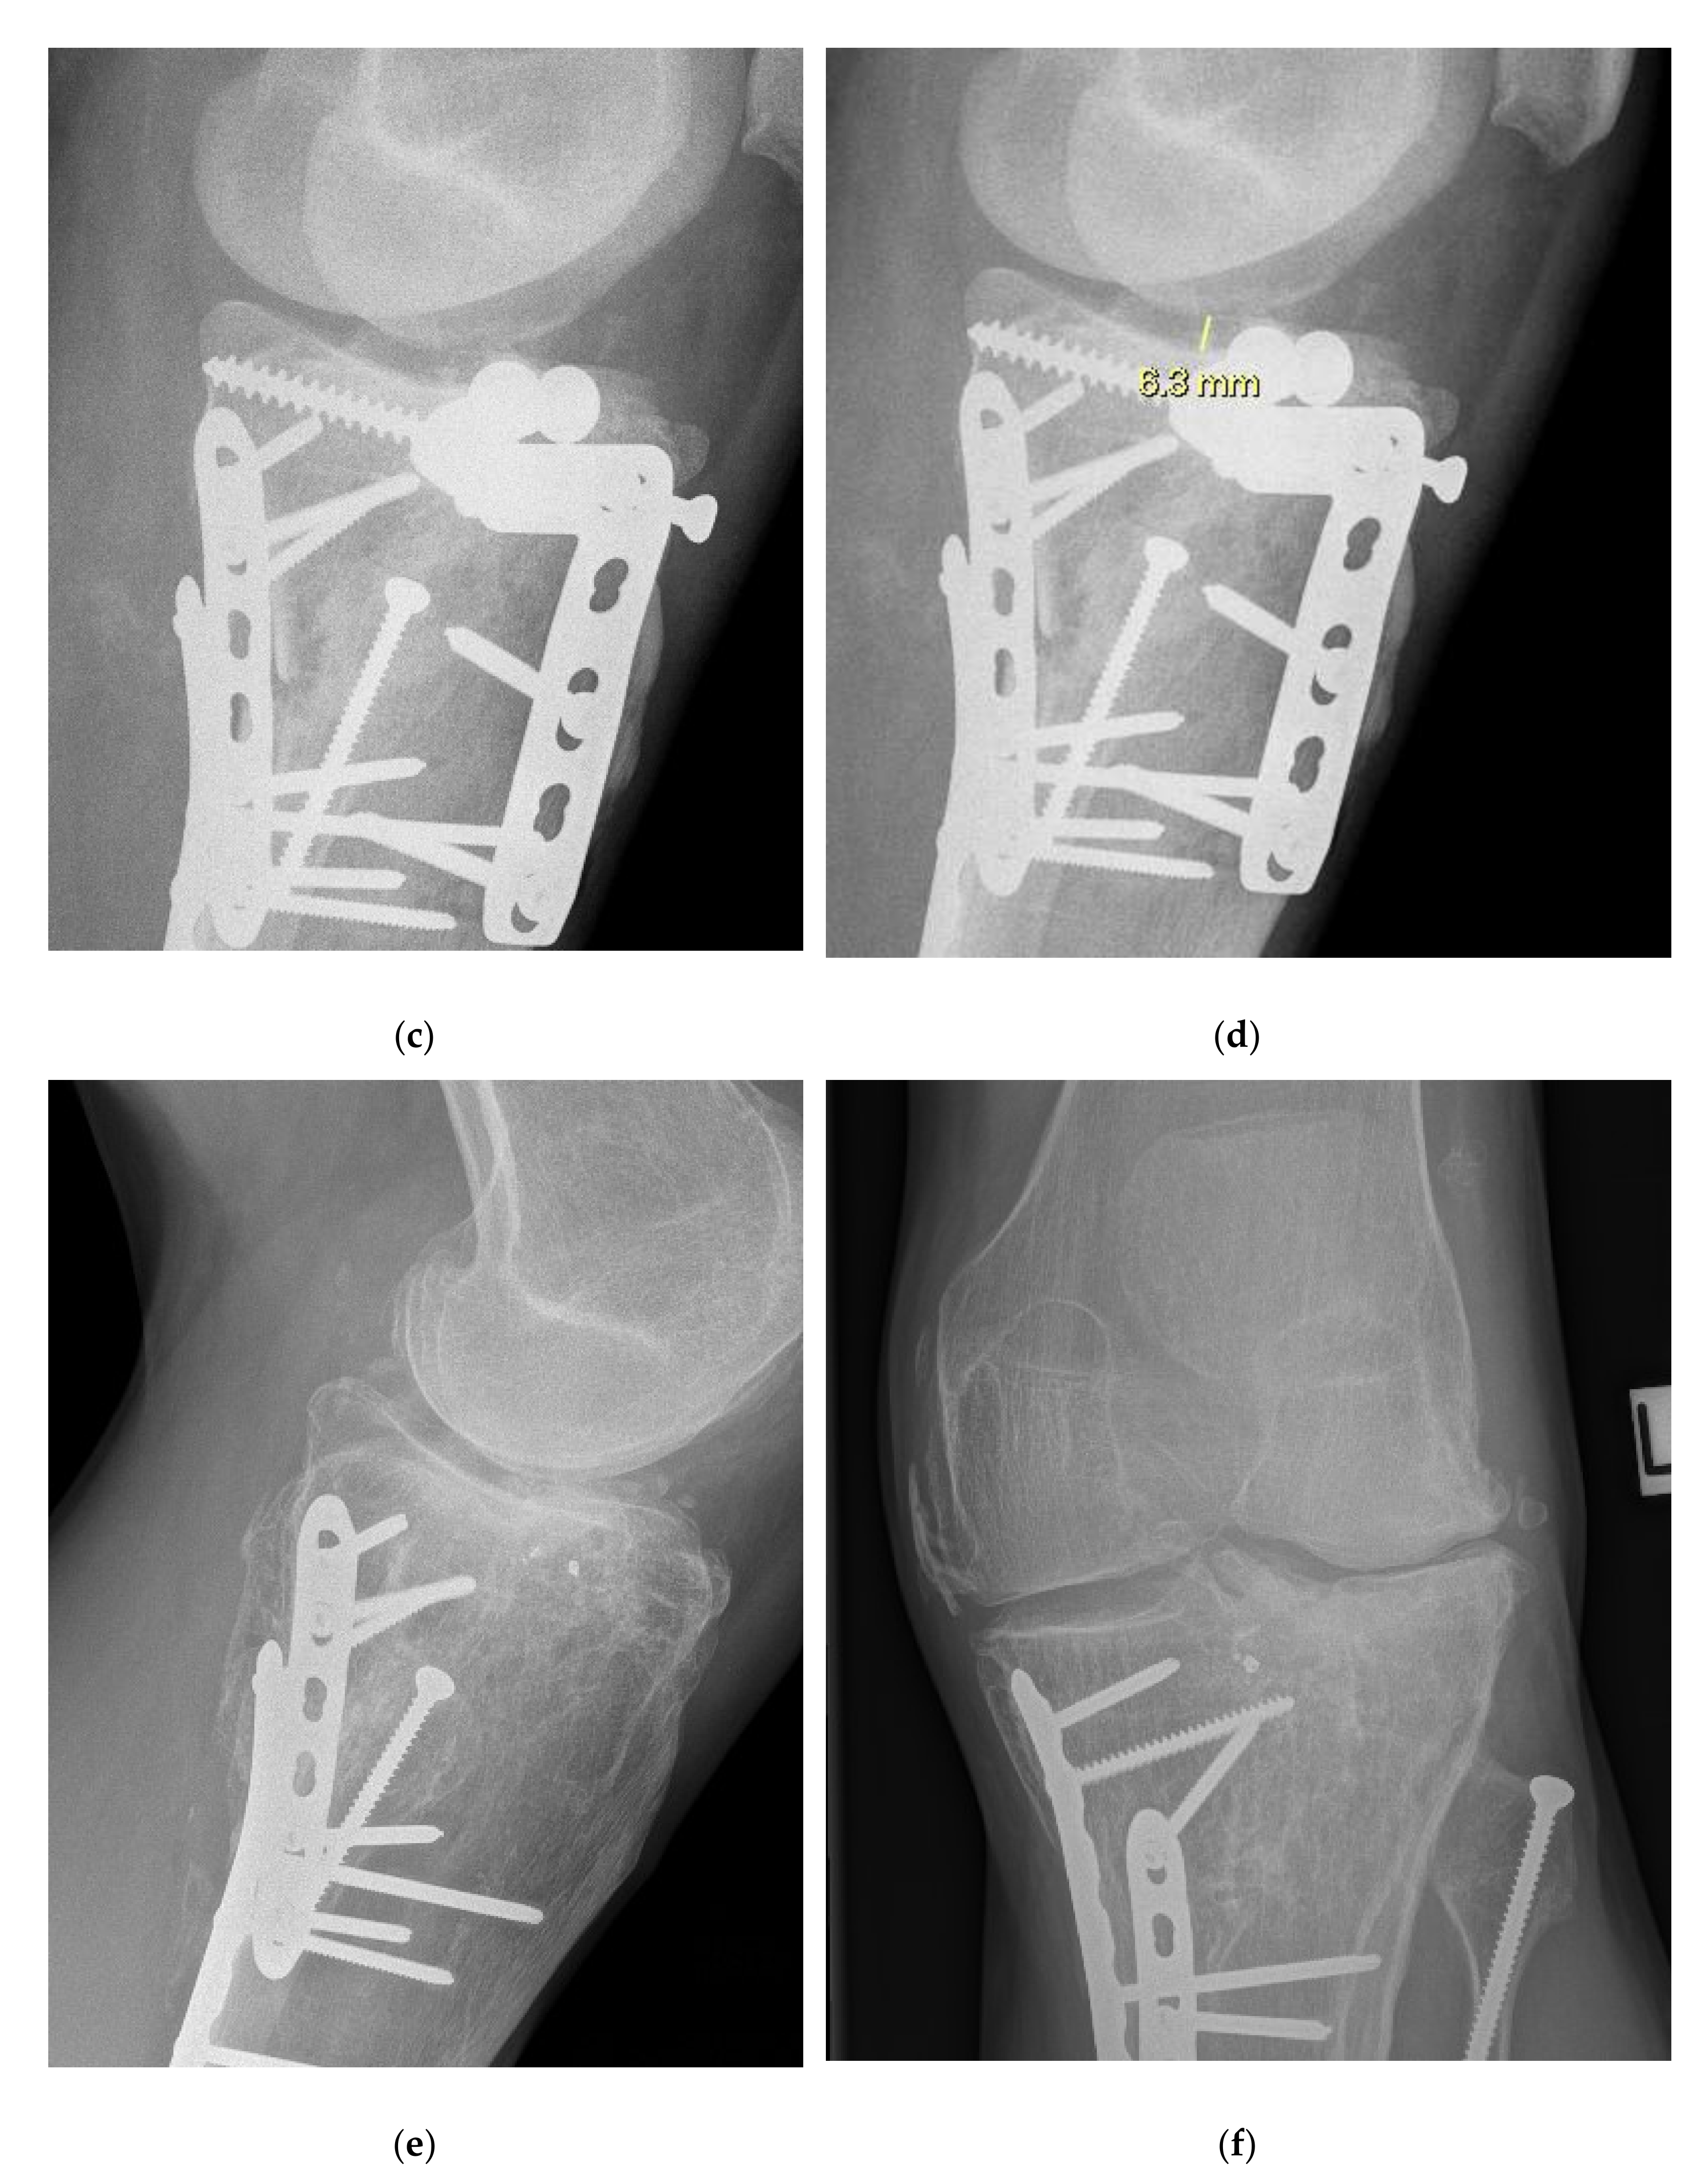

2.2. Radiographic Assessment